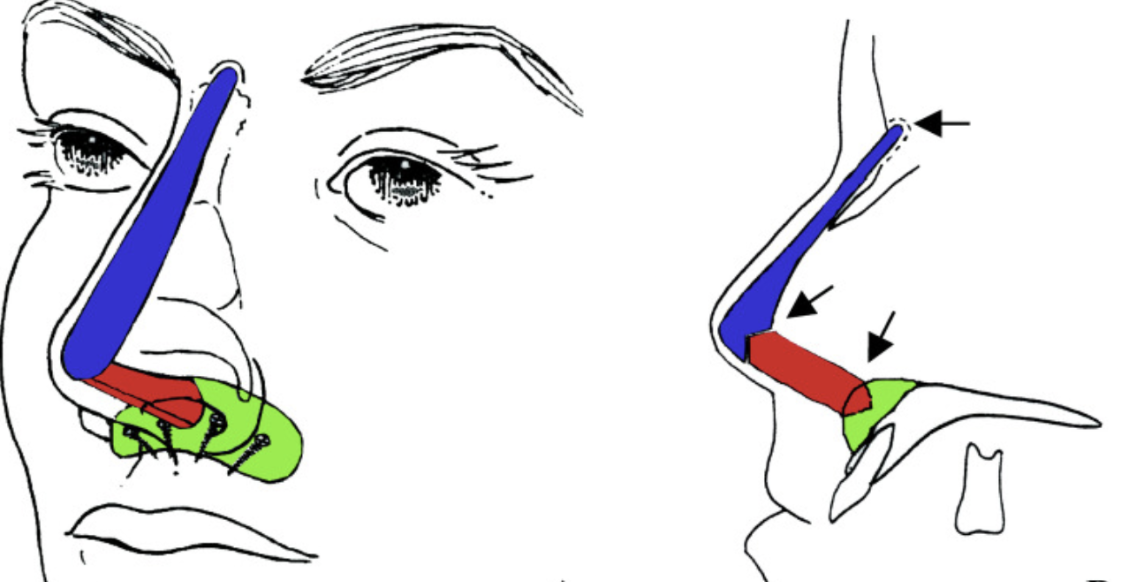

1. L shaped paranasal implantWhat is the anterior nasal spine?

- Implant desgined to mimic the pointiness of the ANS. The implant projecfts the ANS forwards along with the nose base.

- Can be superior to grafting as it provides better contour and results are more predictable.

- This can increase the projection of the septum by 2 mm max according to giant.

- Recommended to be placed during rhinoplasty. Can be placed during bimax as long as it doesnt block the plates, but this is not recommended and can yield unfavorable results.